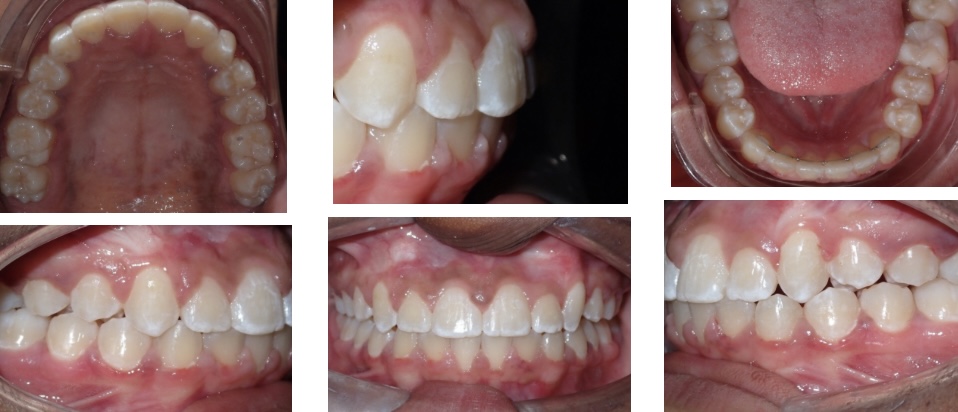

Results. Once the canine teeth have fully erupted, we place full braces on the teeth until they are straightened and in line with the rest of her teeth. The x-ray below shows the canine teeth, now in the corrected positions.

Finally, Lauren had all the braces removed. What a beautiful full smile and a happy patient! Lauren started treatment at age 11. Her treatment lasted two and a half years, allowing time for the canine teeth to move properly and slowly through her bone.